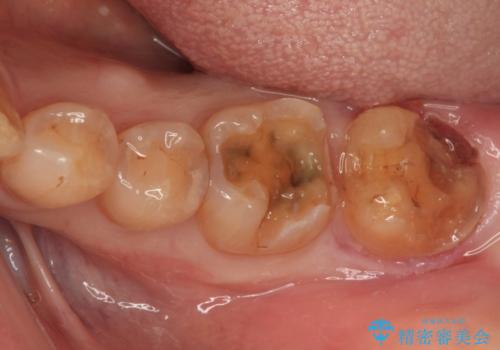

- 奥歯が欠けており、近医でむし歯を指摘されたとのことで来院された患者様です。

1番奥の歯はゴールドインレー周りがむし歯で欠けており、手前の歯はインレーの下にむし歯がある状態でした。